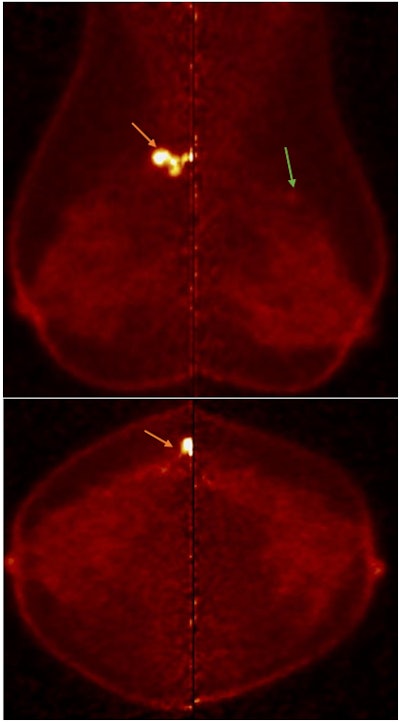

PEM detected multifocality in right breast and excluded multicentricity overestimated by contrast-enhanced mammography (left upper-outer quadrant focal heterogeneous non-mass enhancement was considered suspicious BIRADS-4). Left breast wide local excision revealed sclerosing adenosis and usual ductal hyperplasia. Follow-up revealed no residual suspicious lesions.

PEM performance in the detection of additional multicentric malignant lesions was impressive, with a sensitivity of 95.3%, specificity of 90.9%, and accuracy of 92.7%, the researchers noted. LTB and PUV max both performed very effectively as regards sensitivity and specificity in the detection of ILC, with sensitivity 93% and 95% and specificity 95% and 97%. PEM also showed impressive results in the detection of bilateral malignant lesions with a sensitivity of 100% and specificity of 86.1%, they pointed out.

Contrast-enhanced mammography was carried out in 26 cases, with a sensitivity of 83.3% and a specificity of 75%. PEM was superior to conventional mammography and contrast-enhanced mammography in terms of sensitivity and specificity to multicentricity.